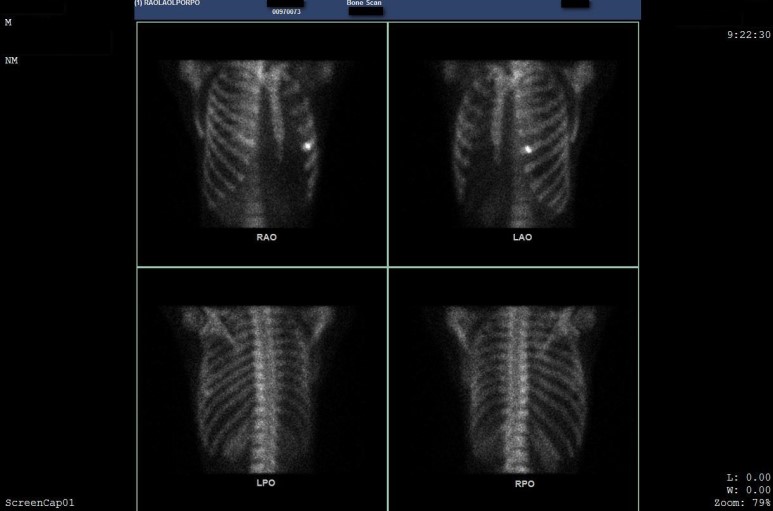

늑골 골절의 진단검사는

본 스캔(Bone scan)이

가장 정확합니다.

뼈 스캔은

뼈를 생성하는 모세포

Osteoblast의 대사를

영상으로 평가하는

진단법인데요.

뼈에 흡수되는

방사성 의약품(MDP)을

정맥주사하면

혈액을 타고 전신에 퍼지게 되고

뼈에 선택적으로 섭취됩니다.

뼈의 혈류량

그리고 재구축, 교체율에 따라서

섭취정도가 결정되는데요.

미세 골절, 염증, 악성종양 등의

질환을 진단할 때

본스캔 Bone scan을

활용합니다.

엑스레이에서 발견하지 못한 골절을 Bone scan에서 진단받았습니다.